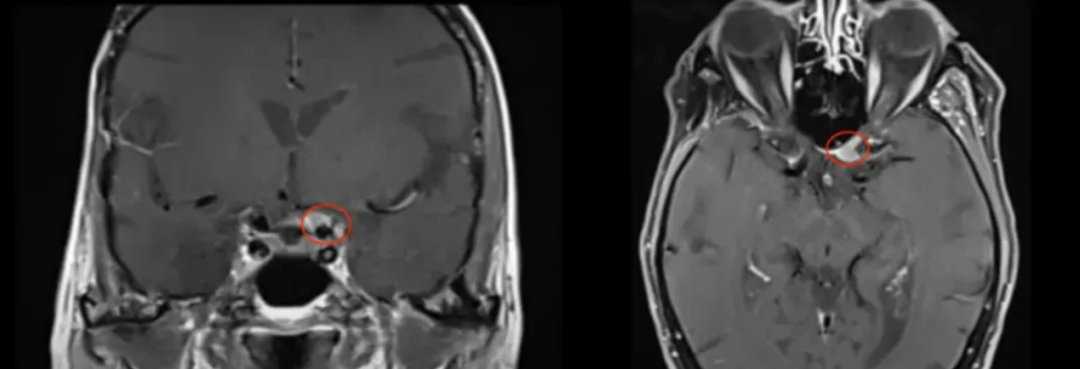

2005年,当时75岁的法国女士卡米尔毅然接受了一次开颅手术,切除了右侧海绵窦脑膜瘤。11年后,命运再次考验她的勇气——左眼视力开始持续下降,检查发现:又一个脑膜瘤正压迫视神经管其下侧,威胁着她最后的光明。

86岁高龄的她选择手术,身边不乏劝阻之声:“何必再冒险?安心静养就好。”可她不愿被肿瘤夺走自己高质量的生活——更何况,福教授经过严谨评估,手术安全可行。

福教授在手术中采用了内镜辅助下右额下入路肿瘤全切术,为她实施了精准的手术治疗。该手术实现了肿瘤的完全切除,达到了辛普森II级标准。术后,患者的视觉功能得到了显著改善,同时嗅觉功能也保持了完好,没有出现脑脊液渗漏的情况。

术前及术后磁共振成像。术前preop(A)和术后Postop(C)显示肿瘤完全切除。